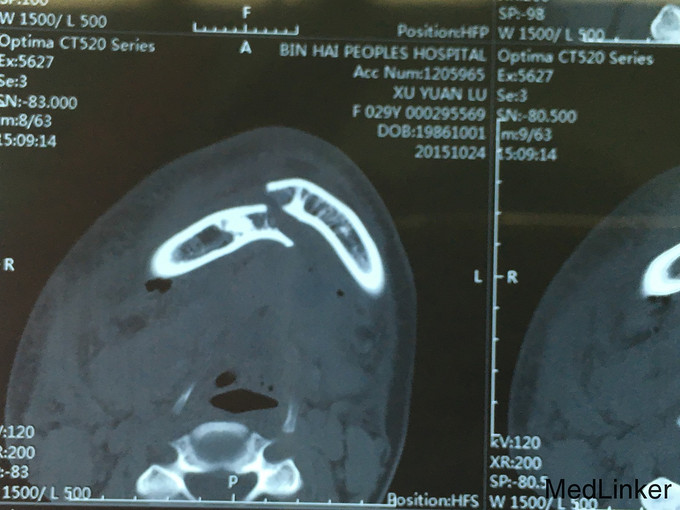

查体:神志清楚,右下颌体部见长约2.0cm开放创口,张口度1.5cm,咬合关系紊乱,右下唇麻木感,43,44间见明显骨折线,异常动度,48松动II,牙龈撕裂,右下颌肿胀,右侧髁状突冲击试验减弱,上颌骨无异常动度,于无异常。 辅查:CT,右下颌骨颏部及下颌角不骨折。

诊断:右下颌骨颏部及下颌角不骨折 治疗:右下颌骨颏部及下颌角部骨折经口内切开复位内固定。

随访:术中咬合恢复良好,被动张口度3.0cm,术后半年、1年、3年随访咬合良好,张口度正常水平。 讨论:下颌角部于外斜线处置接骨板,下缘无需再置接骨板。无需自口外颌下切口,避免损伤面神经下颌缘支。